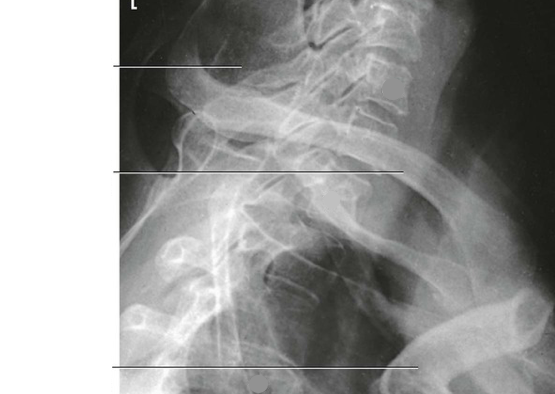

Question 3

Question

Label the image

Image:

449623c7-7518-4f29-a98f-4c2bec32fa04 (image/png)

Answer

C5

mandibular rami

body

inferior articular process

superior articular process

intervertebral disk space

zygapophyseal joint

vertebra prominens